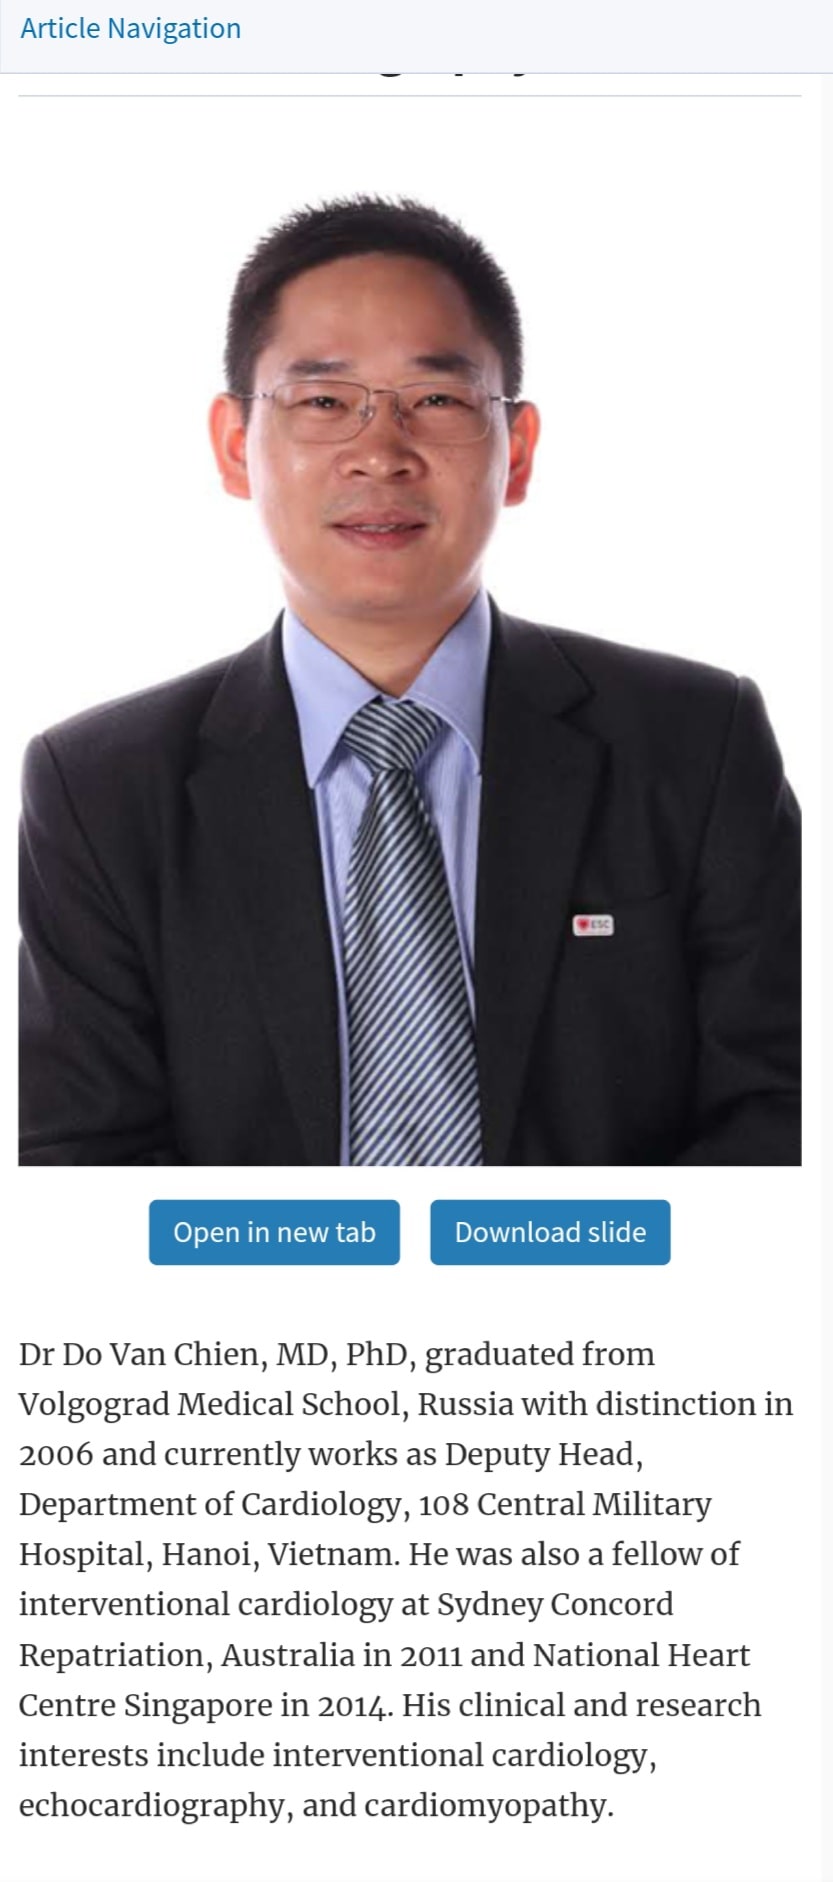

HỖ TRỢ BỆNH NHÂN TIM MẠCH

PGS.TS.BS.Hoàng Anh Tiến

Phó Giám đốc Trung tâm Tim mạch, Phó Trưởng Khoa Nội Tim mạch

BỆNH VIỆN TRƯỜNG ĐẠI HỌC Y DƯỢC HUẾ